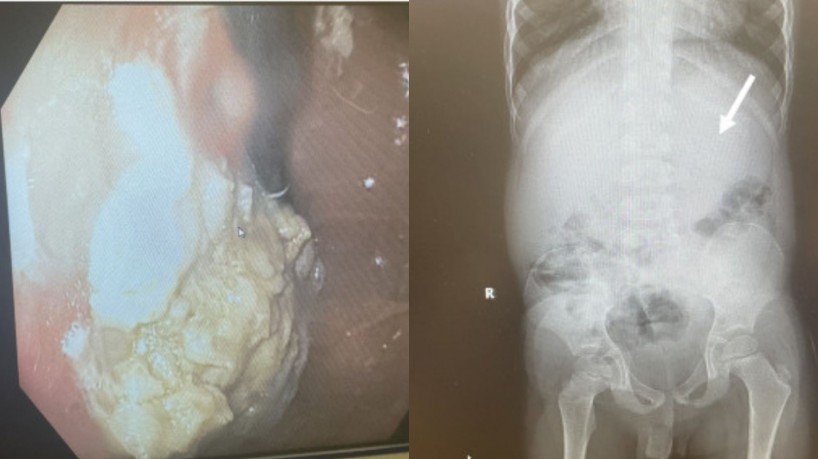

Uma tomografia foi realizada e mostrou que a goma de mascar estava acumulada em seu estômago, atrapalhando o funcionamento do sistema digestivo da criança. O caso foi relatado pela revista médica JEM Reports no início desta semana.

O texto da revista pontuou que a equipe médica teve de retirar a goma de mascar por meio da garganta do menino, optando pela retirada com endoscopia, já que não seria possível dissolver com ácidos e a cirurgia seria arriscada. A tomografia revelou que a criança tinha 25% de massa, bezoar (material não digerido), alojada no estômago.